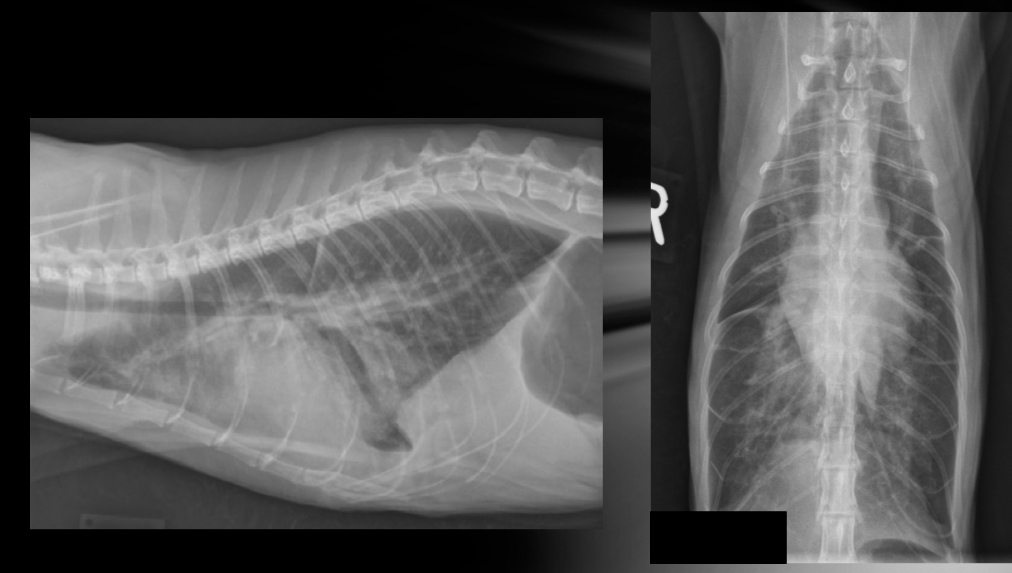

where is the aorta and cd. Vena cava located on VD

Aorta - superimposed with spine and heart on VD

Cd. Vena cava - superimposed with accessory lung lobe in right cd. Thorax on VD

What 2 pathologies can make the cd. Vena cava small/large

- small = hypovolemia or shock

- big = R. CHF —> secondary hepatomegaly and abdominal effiusion

**remember Cd. Vena cava can vary with cardiac cycle and phases of respiration but that is normal **